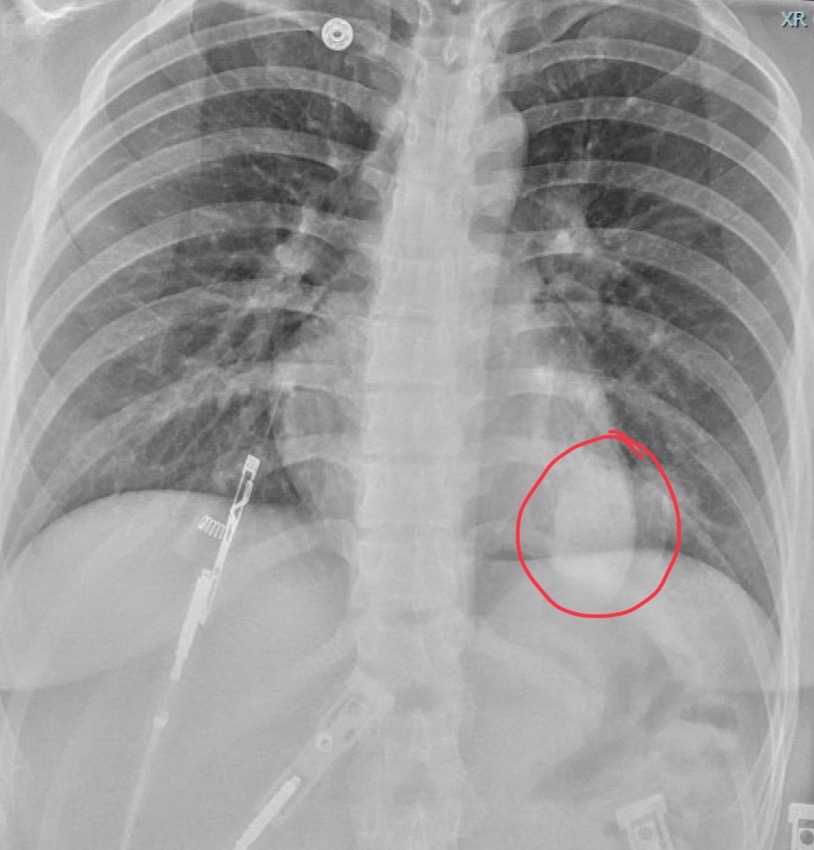

25-year-old female with no background available

Radiolucent area in right lung field with compressive atelectasis of right lung and mediastinal shift to the left consistent with pneumothorax